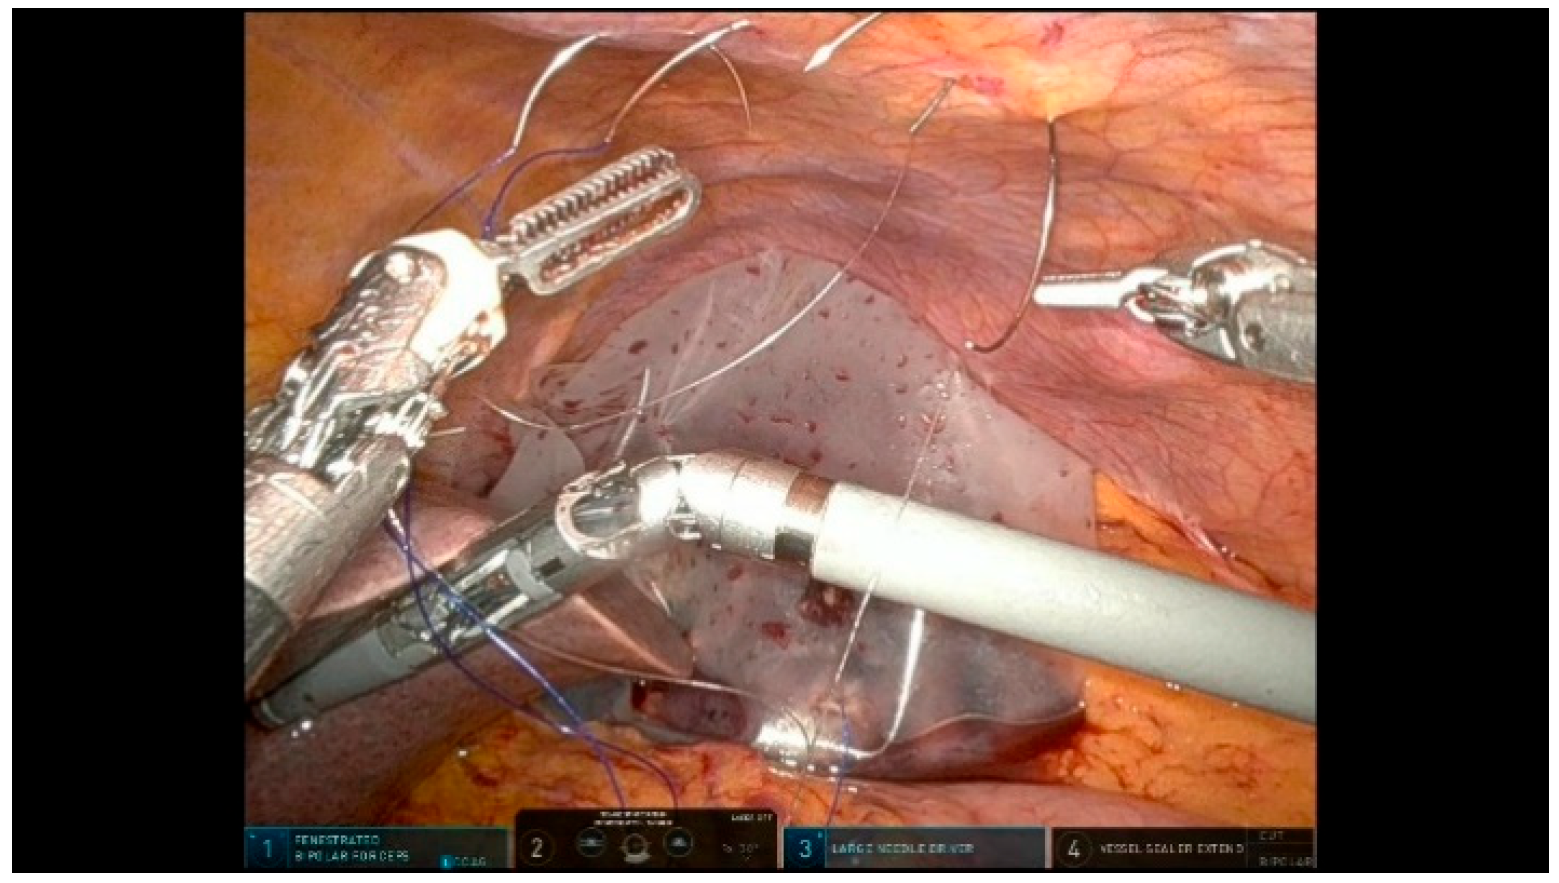

3.2.1. Step 11: Pancreaticojejunostomy

- Duct-to-Mucosa Anastomosis: use a temporary silicone stent to protect the pancreatic duct and facilitate precise suturing.

- Suture Organization: use different colored sutures to prevent tangling and enhance efficiency during anastomoses.